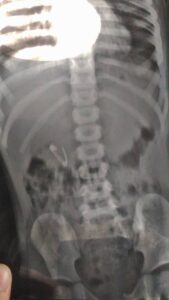

Removal of 2,245 gall bladder stones

Removal of a 1-inch steel rod

Removal of an open safety pin